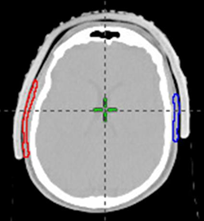

Figure 1F Template marks of repigmented hair were superimposed on the patient’s original planning scan. Red volume is right sided and blue volume is left sided. Axial slice.

Figure 1G Template marks of repigmented hair were superimposed on the patient’s original planning scan. Red volume is right sided and blue volume is left sided. Coronal slice.